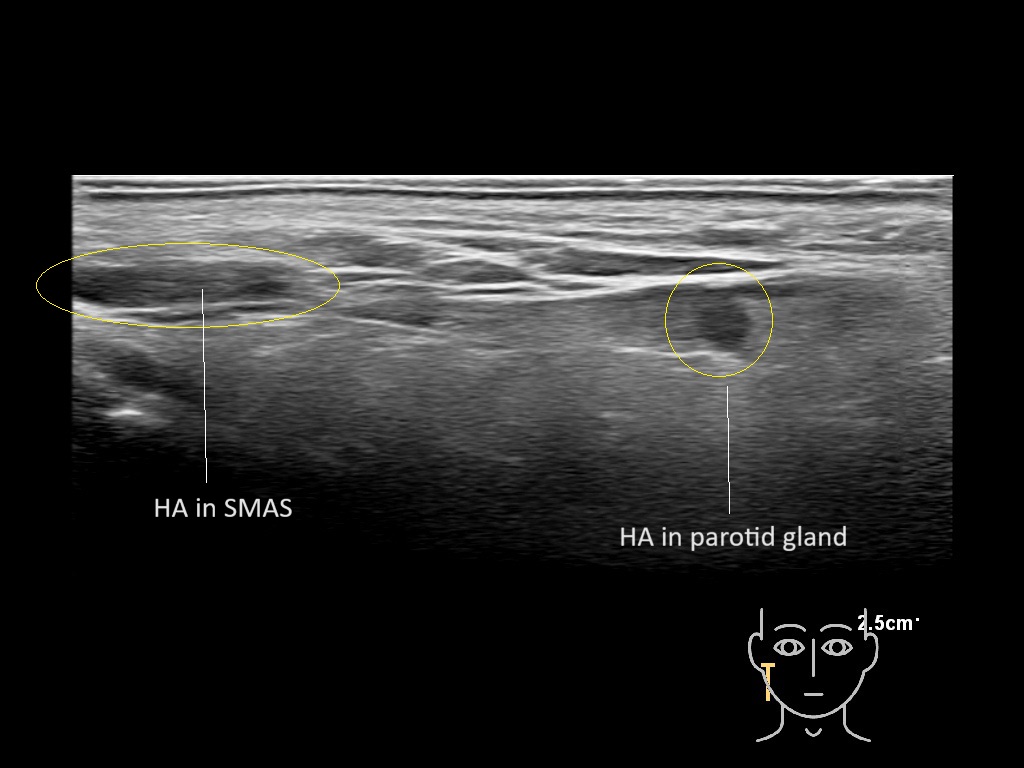

Parotid

Filler injections in the parotid gland may go unnoticed, however, inflammatory reactions and abscesses may occur. Hypervascularity can be seen with color doppler. Filler deposits are supposed to be injected into the superficial fatty layer . The space to inject into this layer may be limited. Routinely we measure a width of 2-4 millimeters with sometimes subcutaneous layers being less than one millimeter thick.

Study the first image to recognize the different layers. If you are sure about the layers, swipe to the second image to view the answer (if applicable).